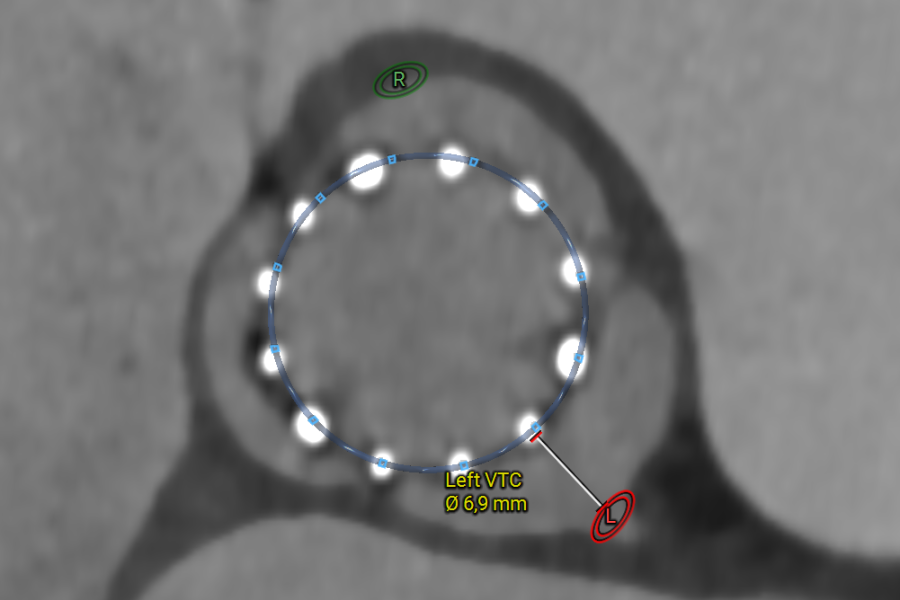

The Valve-in-Valve workflow assists in redo TAV and TAV-in-SAV procedural planning. The workflow is in alignment with the redo TAV app and has additional measurement options for surgical valves as well. This workflow provides specific visualizations and measurements to streamline the process, including:

• Quick index valve diameter measurements to evaluate valve expansion.